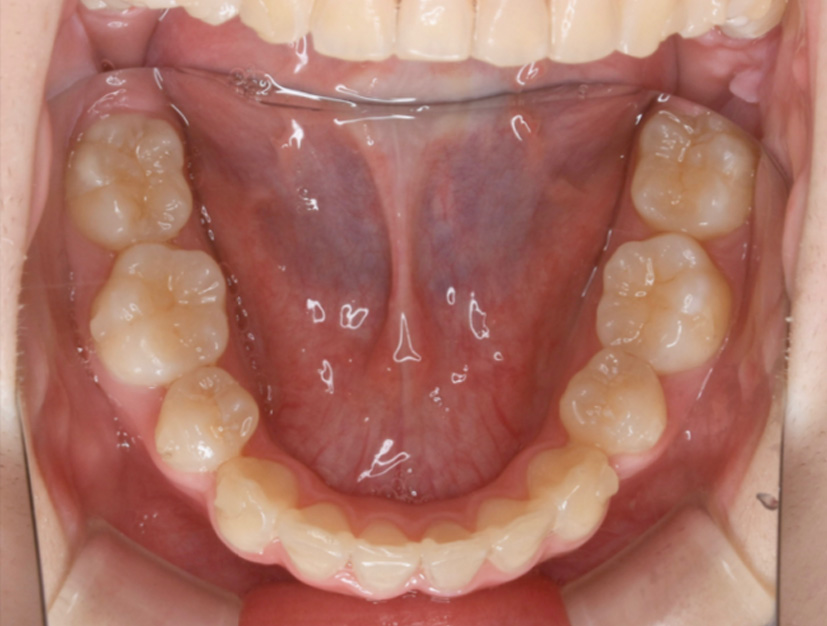

下顎咬合面観